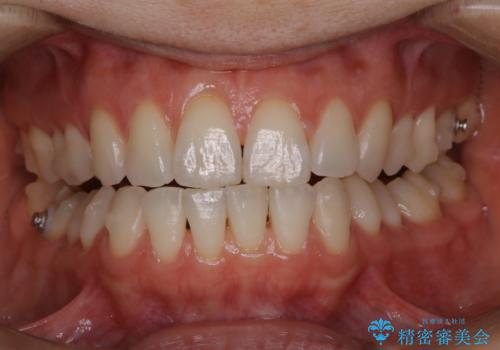

- インビザライン矯正治療中にステインが気になるとのことで来院されました。全体的にステインが付着していたため自費クリーニングPMTC(60分コース)を行いました。

インビザライン矯正治療中は、ご自身の歯にアタッチメントという突起物(効率的に歯の移動を行うため)をつけます。そのため、通常時よりもステインが付きやすい状態になることがあります。

インビザラインは透明なマウスピースなので、ご自身の歯にステインなどが付着していると、見た目に影響してしまうことがあります。